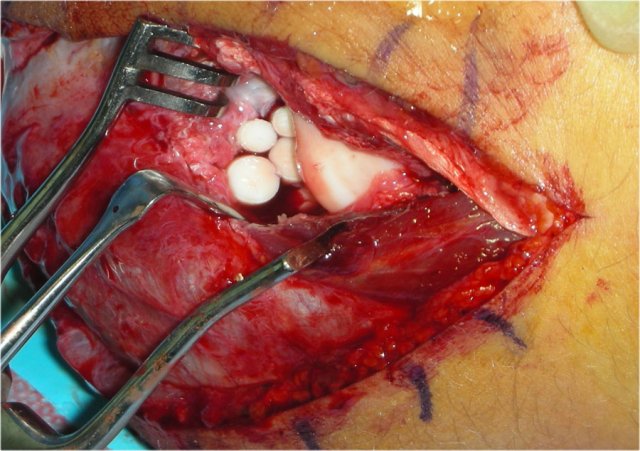

OATS procedure

OATS stands for osteochondral autologous transfer.

Pieces of cartilage and bone are taken out of some other non-weight bearing bone and tranferrred to the capitellum.

In this patient the cartilage is taken from the non-weight bearing part of the knee.

Then holes are drilled in the capitellum and the defects are filled with the autologous bone and cartilage.

Here the hole in the capitellum is filled with four pieces of bone and cartilage.

The radial head is seen opposite the capitellum.